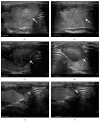

Methods: Ultrasound-guided percutaneous microwave ablation was performed for 90 benign solid thyroid nodules in 75 patients. The volume changes of the nodules were evaluated before and after microwave ablation, and the cosmetic grading and clinical symptoms were assessed as well.

Results: The volume of all the 90 benign thyroid nodules obviously decreased after microwave ablation at 3-, 6-, 9-, and 12-month follow-ups (p < 0.01), while that of the control group increased at the follow-up of 12 months (p < 0.01). The volume reduction rate (VRR) at 3-, 6-, 9-, and 12-month follow-ups was 55.98%, 69.31%, 76.65%, and 84.67% in the MWA group, respectively. The cosmetic problems and clinical symptoms were also improved in the MWA group. All the patients are well tolerated to the procedure. Hoarseness occurred in 2 cases (2.7%) and Horner syndrome in 1 case (1.3%), and 1 patient (1.3%) developed slight burn on cervical skin.